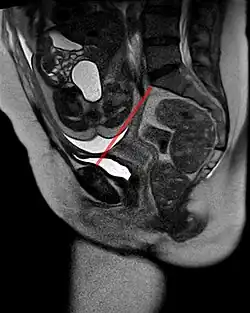

Messung der Conjugata vera obstetrica (rot) in der MRT bei Beckenendlage des Kindes.

• Der Beckeneingang weist eine querovale Form auf (ist also breiter als tief) und wird gebildet durch das sog. Promontorium des Kreuzbeins, der Schambeinfuge und dem Darmbein. Für die Geburtsmechanik entscheidend ist der kürzeste Abstand zwischen der hinteren Symphysenfläche und dem Promontorium, welcher als Conjugata vera obstetrica bezeichnet wird.